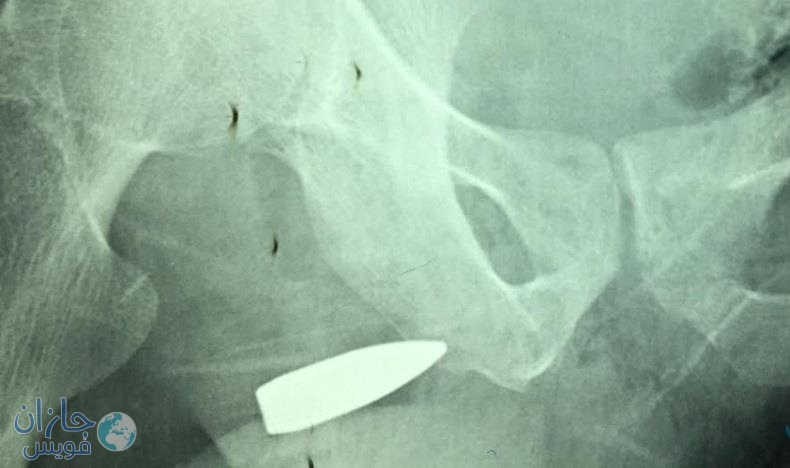

نجح فريق طبي بمستشفى صبيا العام في استخراج طلقة نارية من حوض ثلاثيني تعرض لطلقة نارية تسببت في اختراق الورك الأيسر ومن ثم استقرت في منطقة الحوض.

وأوضح رئيس الفريق الطبي الدكتور حسين بن إبراهيم القاصر استشاري جراحة عامة أن فور وصول المريض لقسم الطوارئ بالمستشفى تم الكشف عليه وإجراء الفحوصات الأولية والتصوير التلفزيوني والأشعة المقطعية, تبين أن الطلقة النارية التي تعرض لها المريض تسببت في كسر الورك الأيسر ومن ثم استقرت في الحوض ما استدعى تدخلا جراحيا من قبل الفريق الطبي المكون من الدكتور عواجي النعمي والدكتور حازم خطاب.

وبين أنه أجريت للمريض عملية جراحية استغرقت ثلاث ساعات تم استخرج الطلقة النارية التي كانت مستقرة بإحدى المناطق التشريحية الصعبة داخل الحوض وذلك لوجود الأوعية الدموية الرئيسية المغذية للحوض والأطراف السفلية, إلا إن الفريق الطبي تمكن – ولله الحمد – من استخراج الطلقة التي تعرض لها المريض دون أن تتسبب بأي نزيف أو مضاعفات له, وتم متابعة المريض بعد إجراء العملية وتم التأكد من استقرار حالته الصحية.